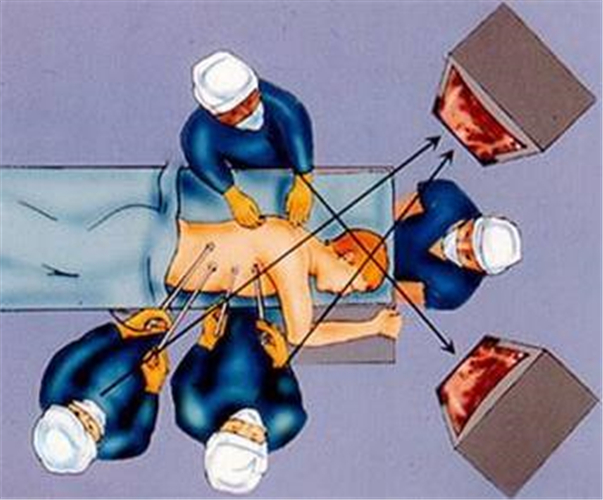

結核性胸膜炎做穿刺的

結核性胸膜炎做穿刺